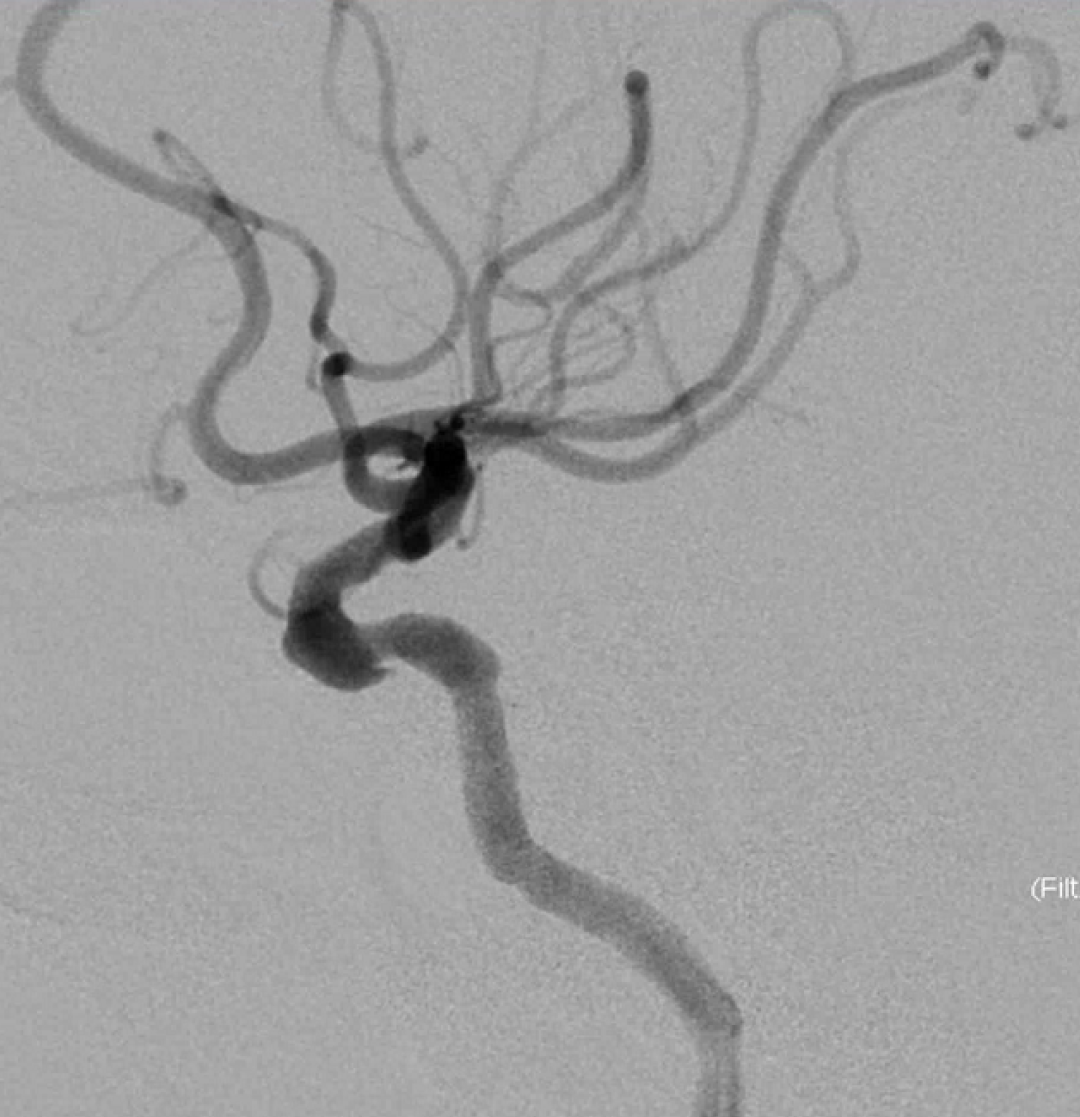

左侧瘤体形态欠规则,4mm×30mm Streamline 优先处理左侧动脉瘤

术后3月复查,瘤体未见显影,载瘤动脉通畅

同期4mm×20mm Streamline 进一步处理右侧动脉瘤